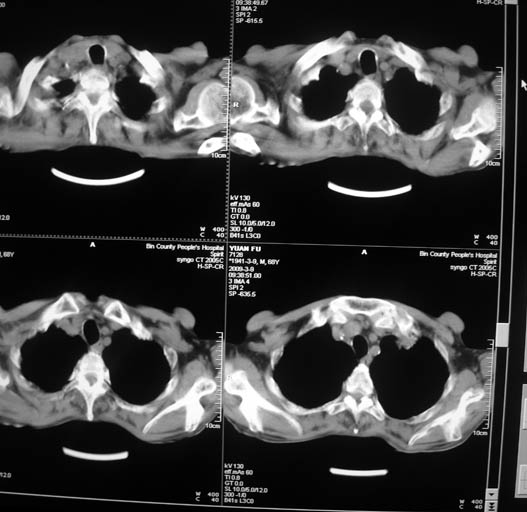

标题: CT18577:男,68岁,左肺占位。 [打印本页]

标题: CT18577:男,68岁,左肺占位。

男,68岁,左上肺占位,肺门淋巴结转移?